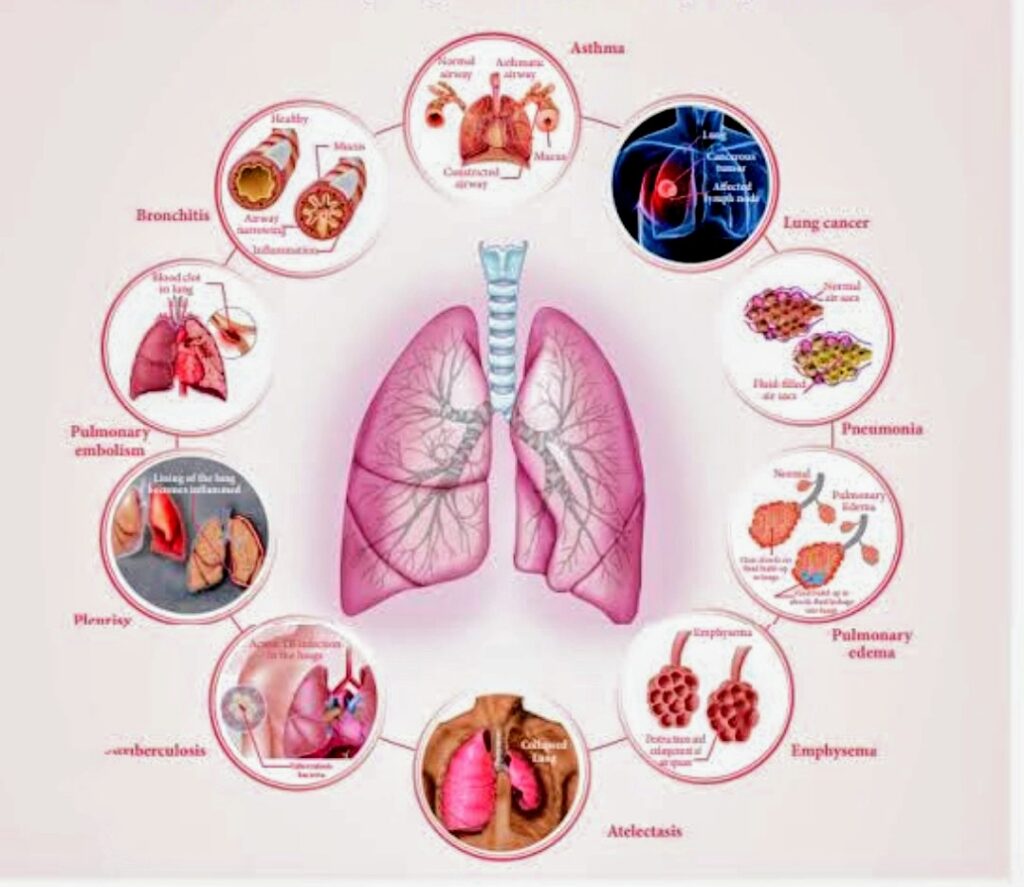

श्वसन संबंधी बीमारियाँ वे बीमारियाँ होती हैं जो हमारे फेफड़ों और श्वसन तंत्र को प्रभावित करती हैं। ये बीमारियाँ सांस लेने की प्रक्रिया में रुकावट पैदा करती हैं,

जिससे व्यक्ति को सांस लेने में कठिनाई होती है। ये सामान्य सर्दी-जुकाम से लेकर अस्थमा, क्रॉनिक ऑब्सट्रक्टिव पल्मोनरी डिजीज (COPD), निमोनिया, और फेफड़ों के कैंसर तक हो सकती हैं।आज हम श्वसन संबंधी बीमारियों पर चर्चा करेंगे, जो दुनियाभर में तेजी से फैल रही हैं। क्या आप जानते हैं कि हर साल लाखों लोग इन बीमारियों से प्रभावित होते हैं?

श्वसन संबंधी बीमारियाँ वे बीमारियाँ होती हैं जो हमारे फेफड़ों और श्वसन तंत्र को प्रभावित करती हैं। ये बीमारियाँ सांस लेने की प्रक्रिया में रुकावट पैदा करती हैं,

जिससे व्यक्ति को सांस लेने में कठिनाई होती है। ये सामान्य सर्दी-जुकाम से लेकर अस्थमा, क्रॉनिक ऑब्सट्रक्टिव पल्मोनरी डिजीज (COPD), निमोनिया, और फेफड़ों के कैंसर तक हो सकती हैं।